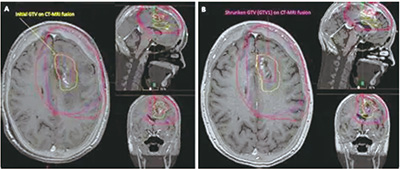

FET-PET在诊断复发性胶质母细胞瘤方面的特异性CE-T1MRI。为了评估基于FET-PET的靶体积勾画与CE-T1MRI相比,是否能改善拟再次放疗的复发性胶质母细胞瘤患者的结局,该项在德国15个放射肿瘤中心进行的、多中心、开放标签、平行分组随机研究(GLIAA/NOA-10 ARO2013-01)纳入≥18岁的、卡氏评分≥60%的、大体下WHO分级为4级(1~6 cm)的、复发性胶质母细胞瘤患者,等比分予基于FET-PET或CE-T1MRI的靶体积勾画,随后再次放疗(39 Gy/13 f),并按照首次放疗时间、既往化疗、肿瘤直径、MGMT状态和计划的化疗进行分层。